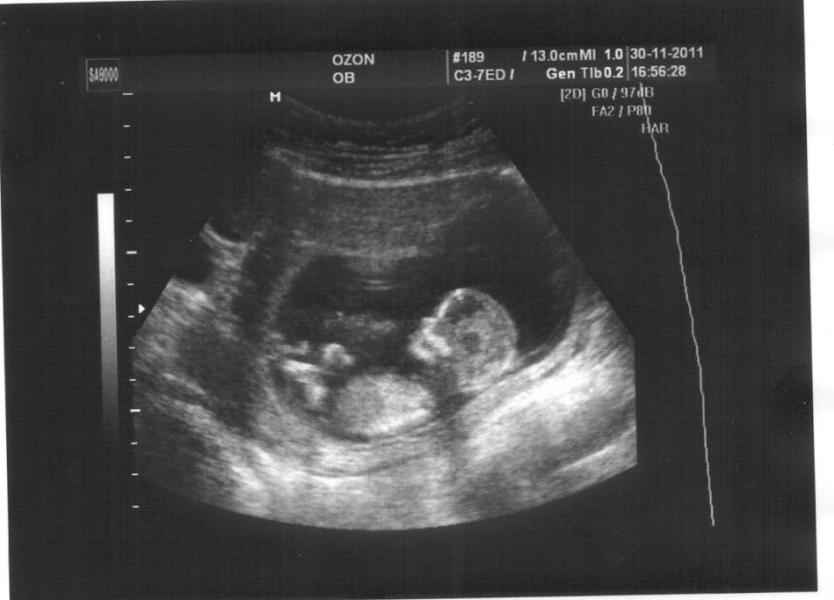

#тема#как часто вы ходили на УЗИ? и как вы считаете УЗИ при беременности вредно? Стоит придерживаться только скрининга? Просто ситуации разные... И иногда БЕРЕМЕНЯШКИ за многое переживают... И им хочется быть спокойными сходив на узи..

Делала чаще скрининга в разумных пределах(раз 6/7) если сильно переживала, обязательно смотрела как там малыш

Делала раз в 10 дней до 19 недели по показаниям, врачи говорили не вредно

Делала по направлениям 3 раза: подтверждение , 1-2скрининг. После ходила для себя сделать 3D фото малыша. Сейчас назначил врач ещё одно узи (плановое).

Раз 8 делала , уже сбилась со счёта . Врач сказала это не вредно . Мне как заболит живот так и хожу.

Я уже успела 4 раза побывать, для подтверждения беременность, при постановке на учёт, показать папе, и сегодня..чувствовала неделю дискомфорт, переживала.

Я хожу раз в неделю .Мой Гениколог говорит ,что не вредно .Говорит ,что только деньги я зря выкидываю .Мол показаний нет слава богу .А мне плевать .Мне на это денег не жалко .Сделала и спокойно себя чувствую

3 раза ходила))) 1 раз для подтверждения беременности, 1ый скрининг и 2-ой)))) 26 недель сейчас)вроде еще одно узи должны назначить) не вижу повода ходить часто)